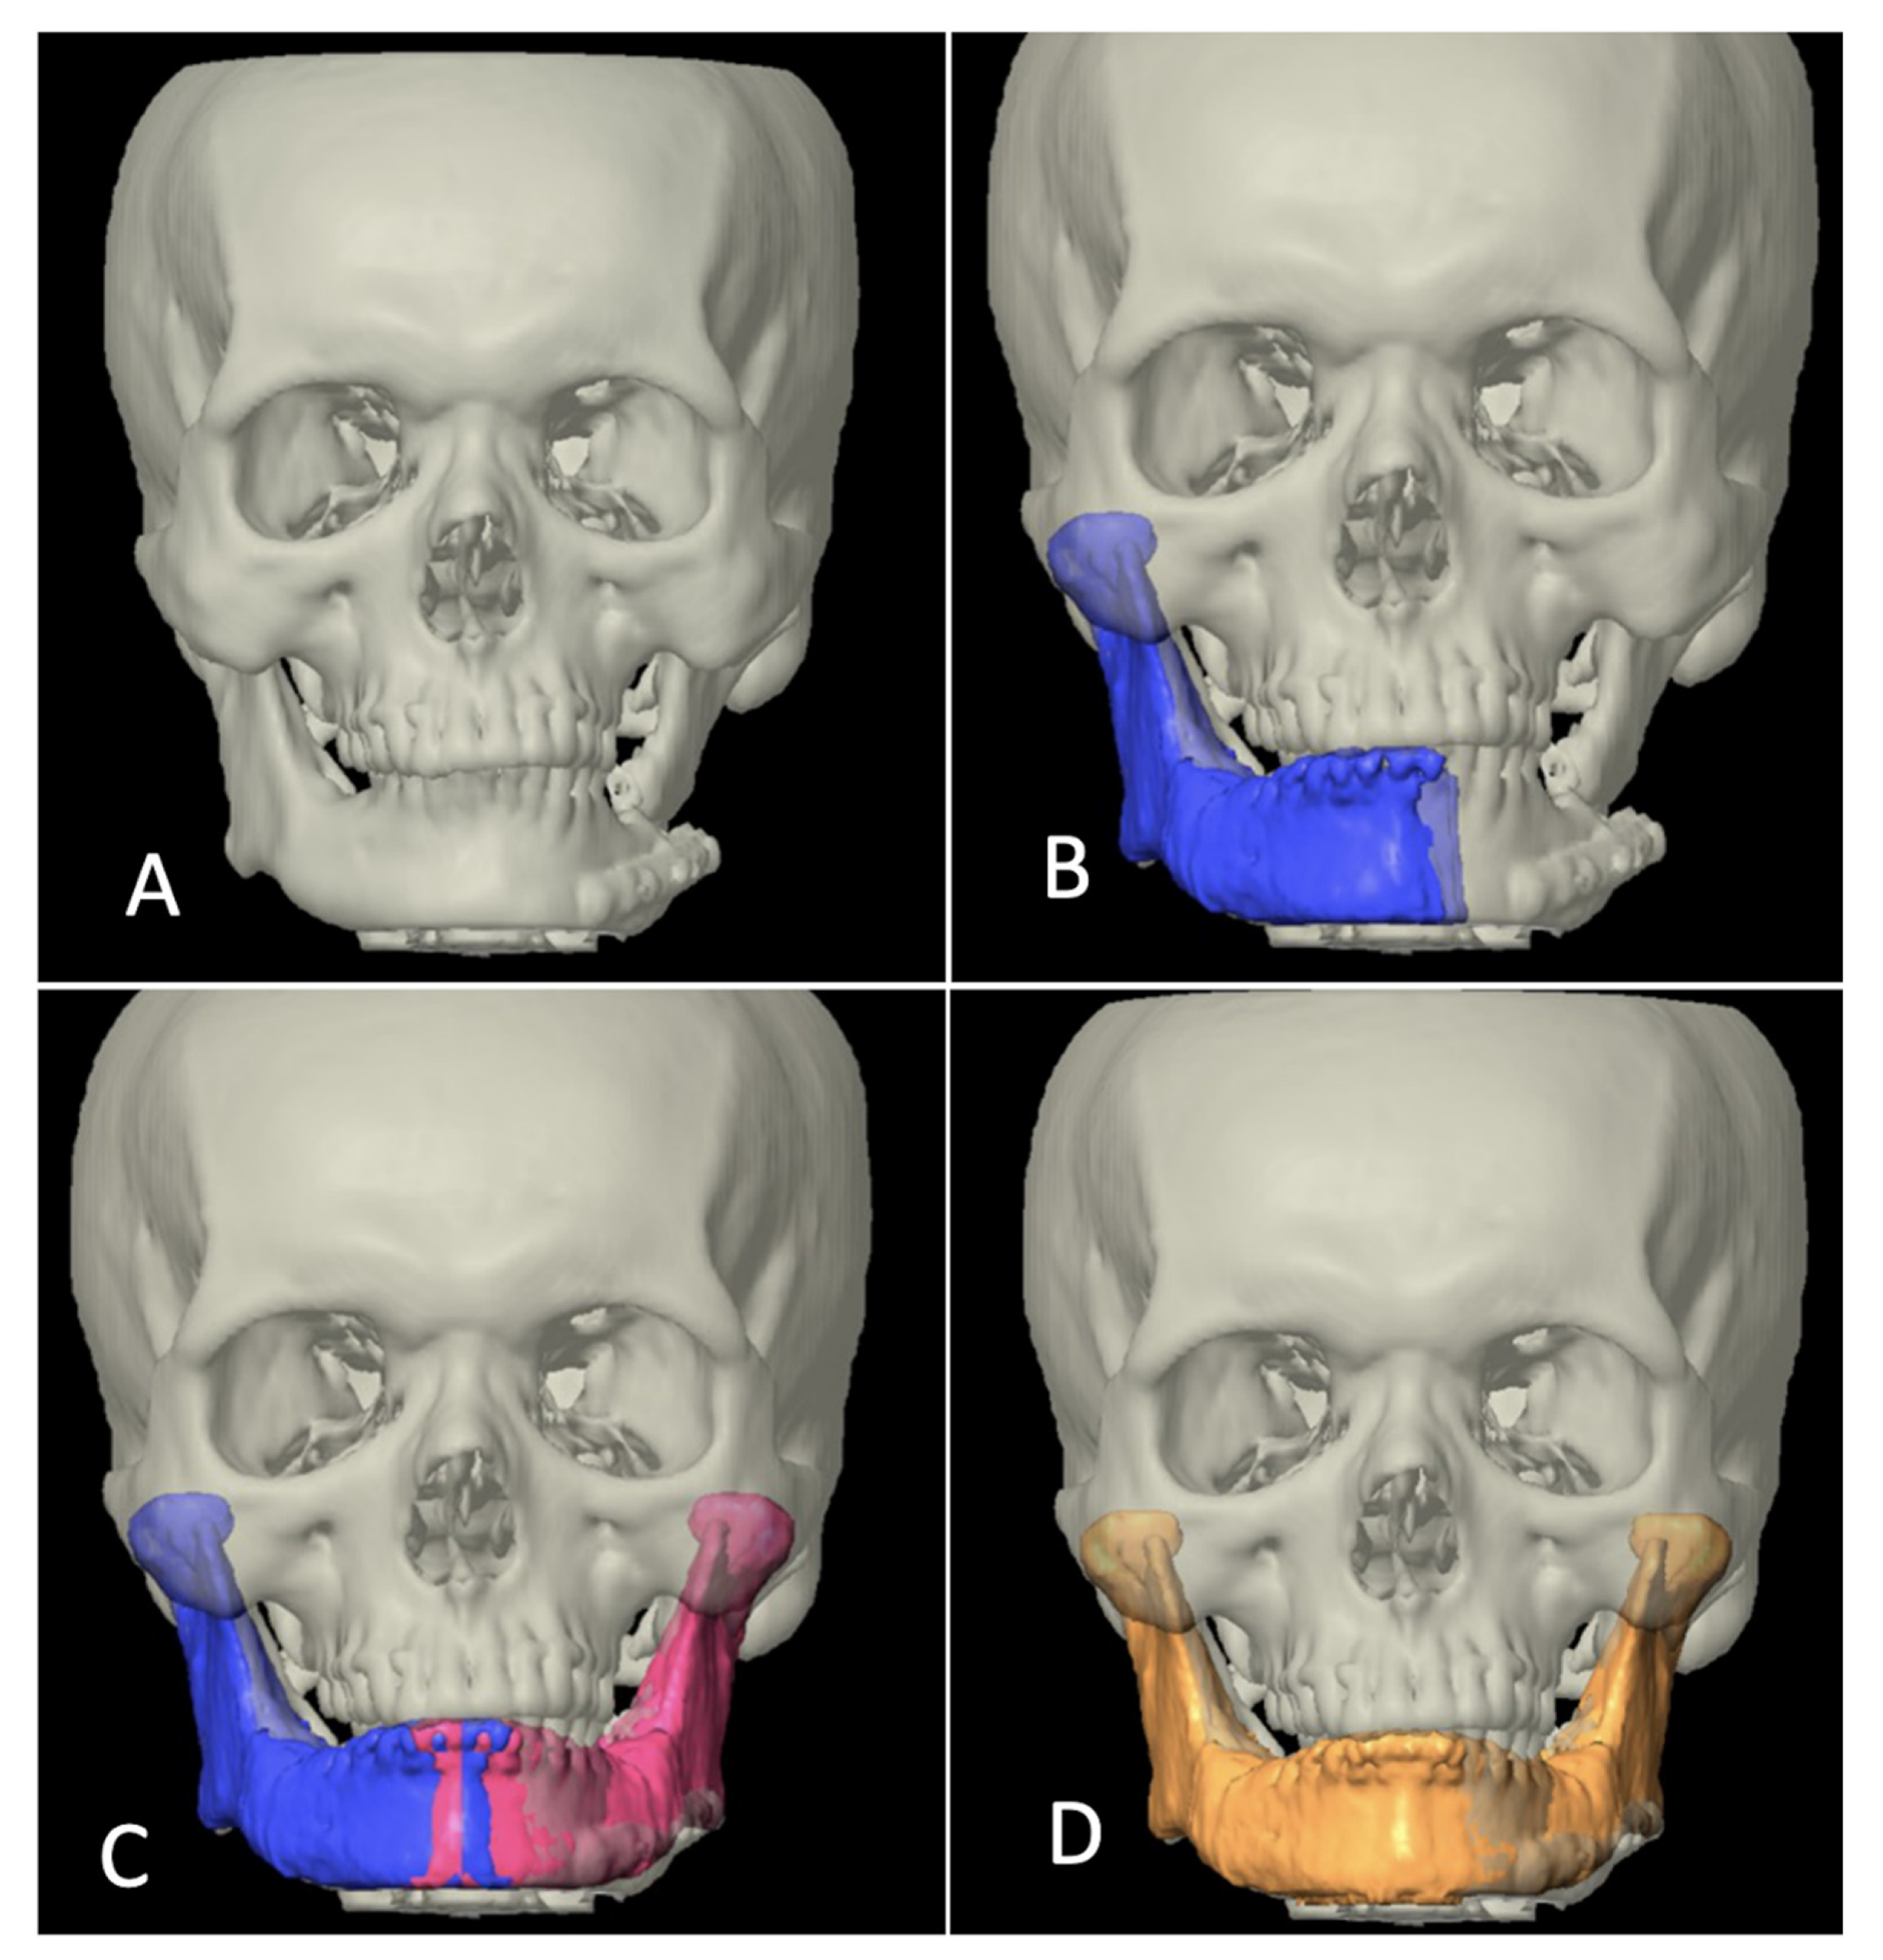

In category II, the ablative defect extended past the midline. CT/MRI taken before the primary surgery were superimposed over the postoperative/current imaging, necessary realignment of the residual segment was carried out and then mirrored. The unresected portion from the previous imaging was then used as template to manually delineate the mandibular contour to reproduce a whole mandible (Figure 3).

Figure 3.

Designing template in category II. (A) 3-dimensional view of defect. (B) Segmentation of the remaining mandible on the left side (blue color). (C) Mirroring to the right side (red color). (D) Superimposing the current CT scan axial view to previous MRI. (E) Drawing the residual defect (red). (F) 3-dimensional view of virtually reconstructed defect (red). (G) Merging the segmented part, mirrored part and drawn part to form whole simulated mandible for printing (purple color).

Category III included the cases where defect crossed the midline, but since primary surgery was carried out elsewhere, previous imaging data were not available. In those cases, the authors’ institution’s radiology data bank was manually searched for the mandibular anatomy that most closely mimicked the patient’s mandible in consideration for reconstruction. The inter-condylar dimension was taken as a reference for transverse dimension whereas a normal value of FH-NPog angle (angulation between Frankfort horizontal plane and Nasion-Pogonion line) was taken as a sagittal reference to look for a close match. It was also made sure that the mandibular arch form of the chosen data grossly coordinated with the maxillary arch form of the patient, i.e., in class I skeletal relation (Figure 4).

Figure 4.

Designing template in category III. (A) 3-dimensional view of defect. (B) Appropriate mandibular anatomy selected from radiology data bank taking intercondylar distance as horizontal reference (red color). (C) Frankfort Horizontal Plane (FHP)-Nasion Pogonion (NPog) angle used as sagittal reference (87 ± 4 degrees being the normal range). (D) Arch form coordination approximately matched with maxilla. (E) Condylar anatomy of database matching the patient’s original condylar anatomy (red).